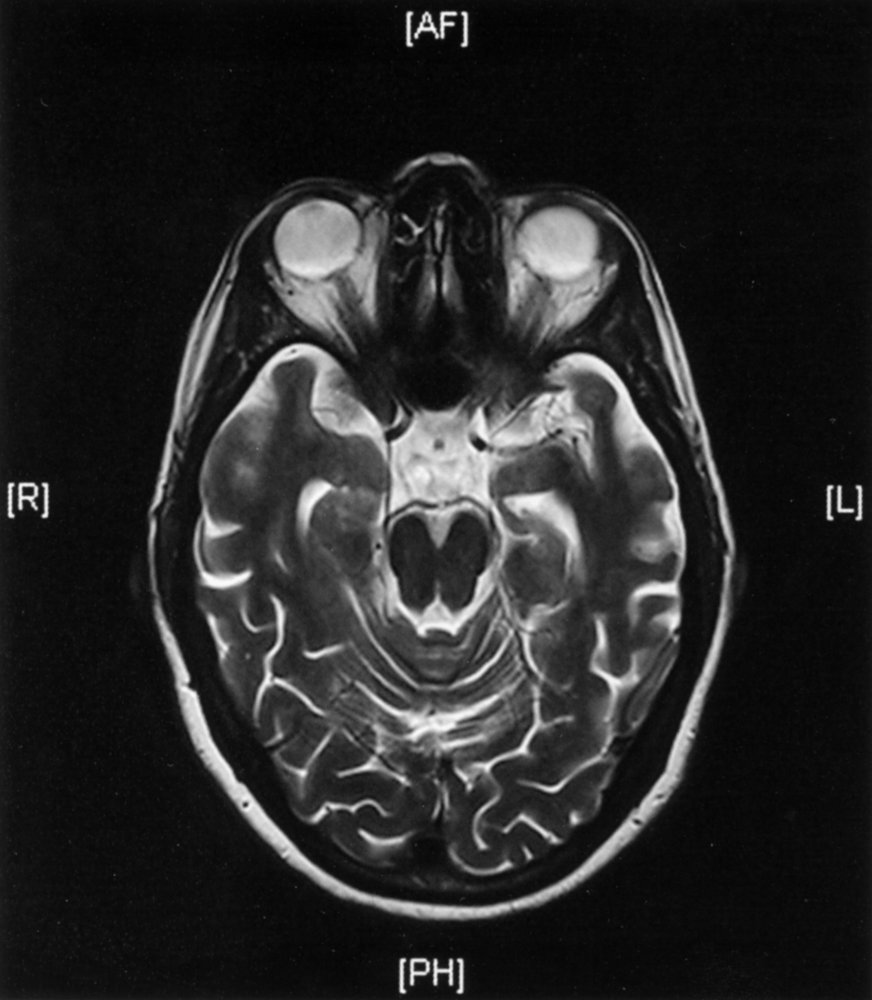

MRIbrain [7][8]

• Indication: all patients as part of the initial evaluation of major neurocognitive disorder

• Supportive findings

• Signs of generalized or focal cerebral atrophy

• Enlarged ventricles (ventriculomegaly)

• Narrowing of gyri

• Prominent cerebral sulci (hydrocephalus ex vacuo)

• Disproportionate atrophy of the medial temporal lobe including the hippocampi, amygdala, cingulate cortex, and parahippocampal gyrus

Macroscopic

• Cerebral atrophy

• Damage to the hippocampus and parahippocampal cortex (medialtemporal lobe structures) is the earliest gross pathological change.

• Diffuse cortical atrophy occurs as the disease progresses.